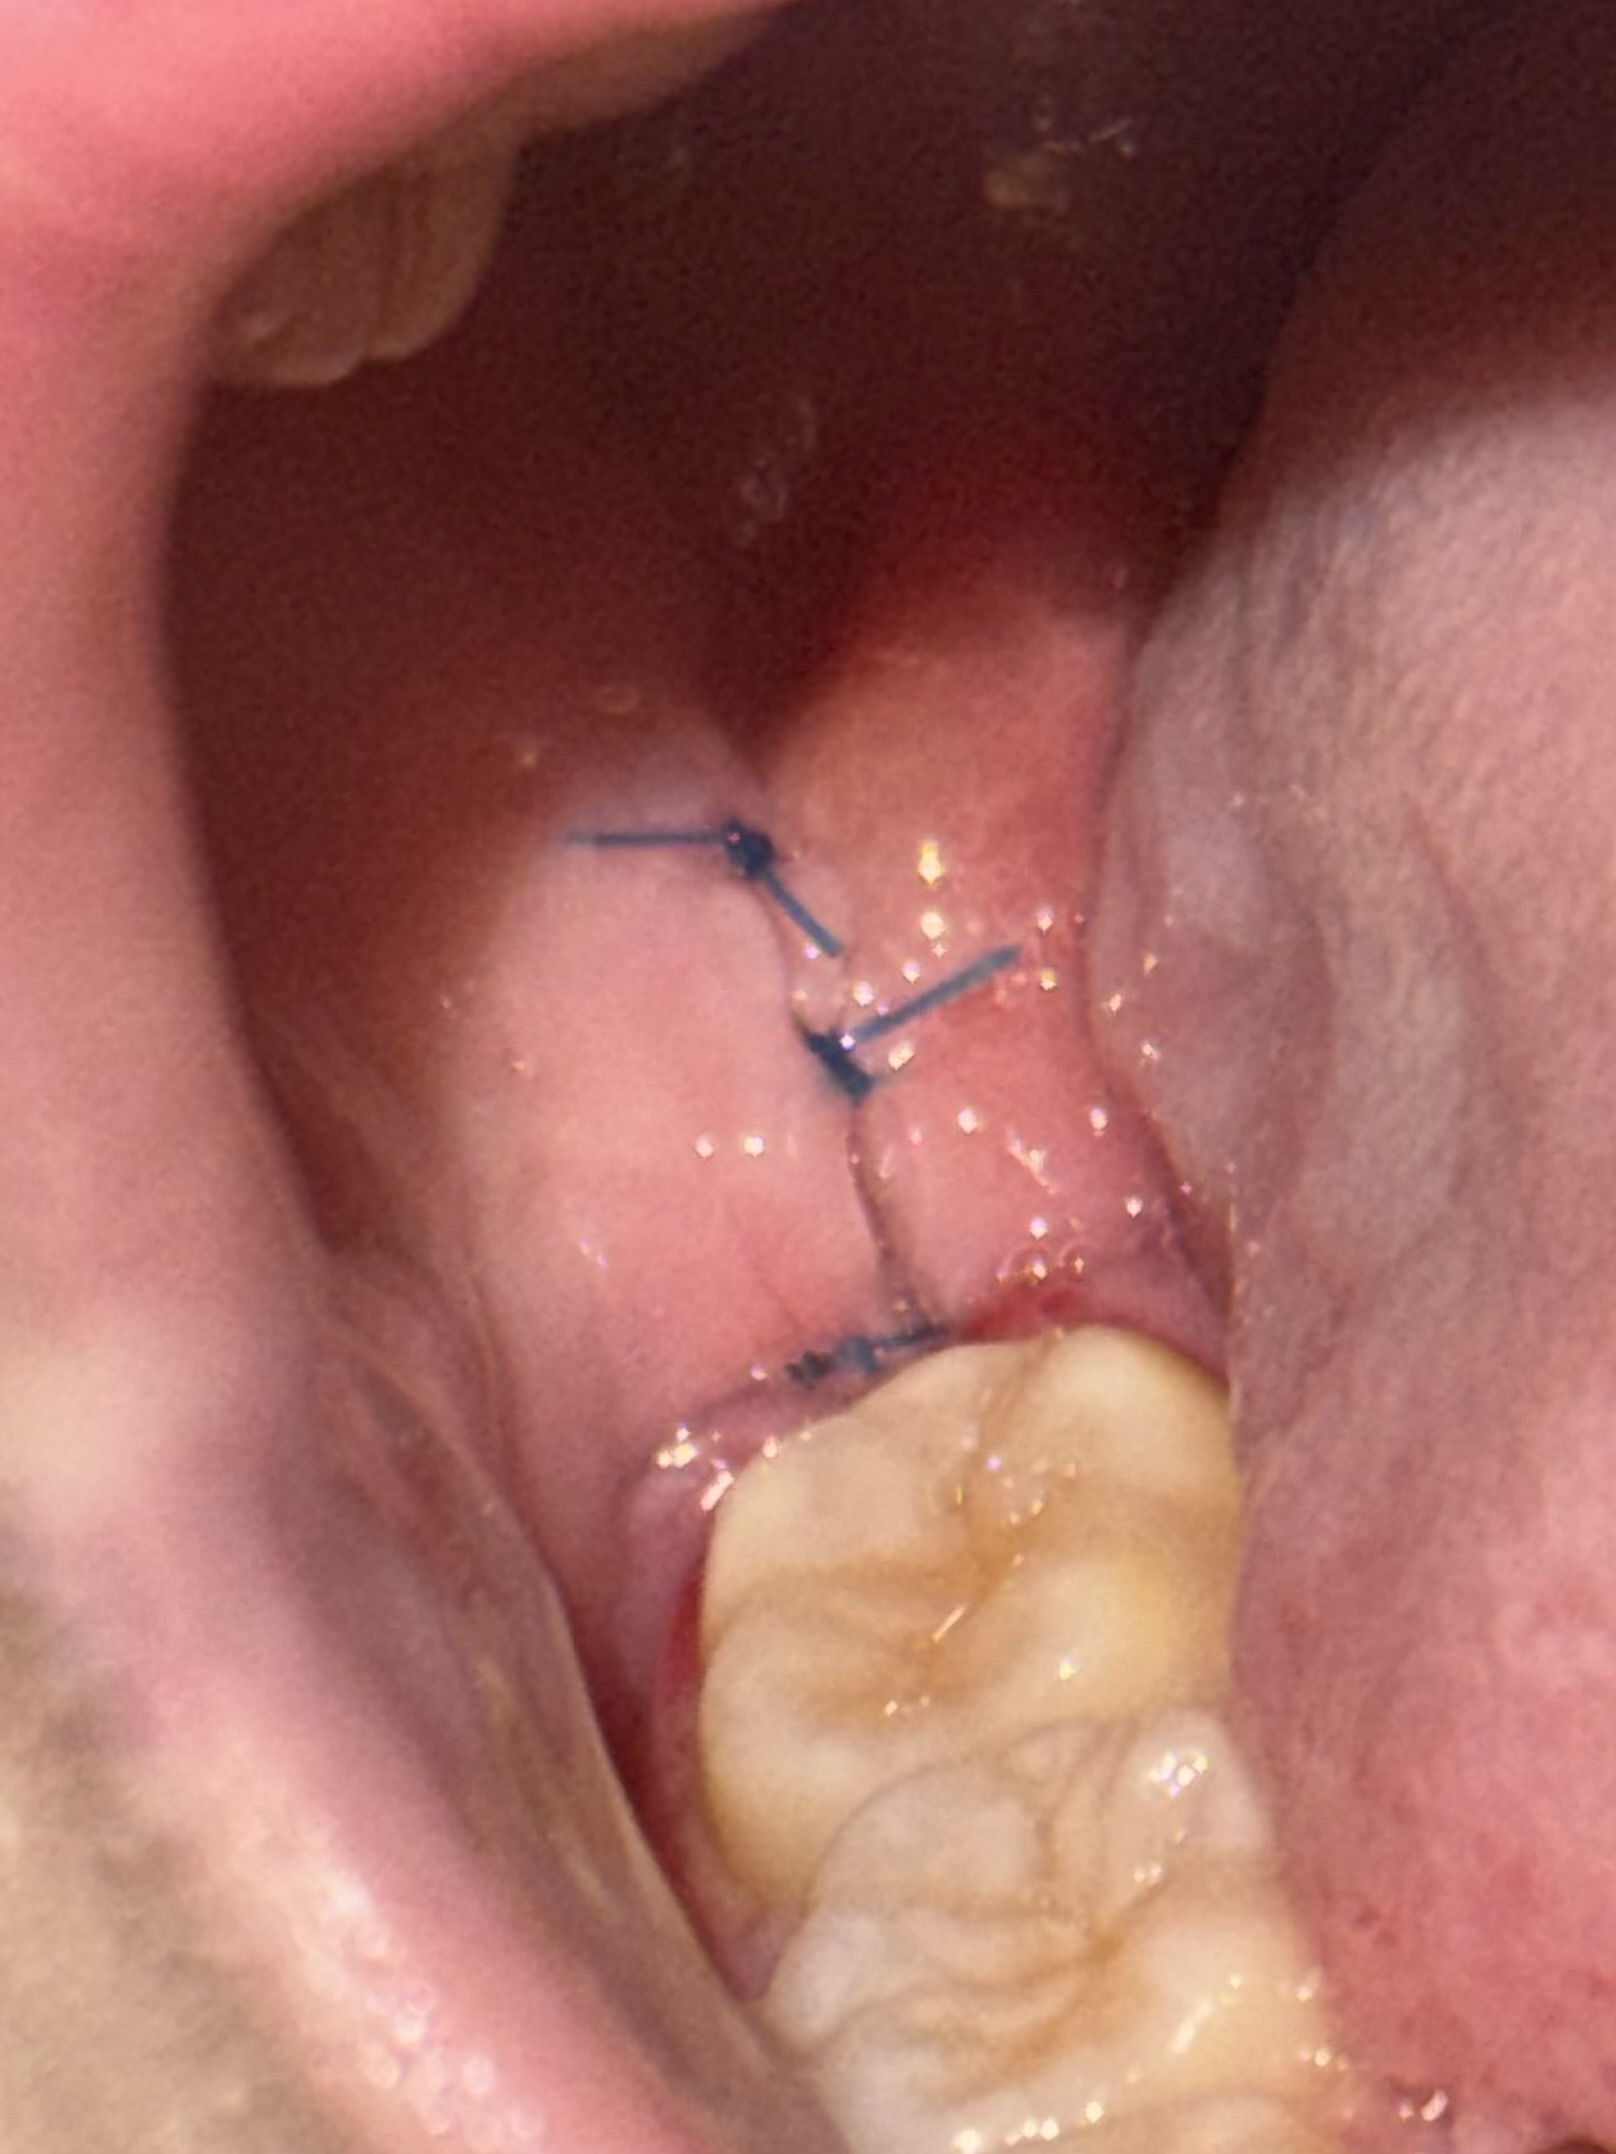

5日前に右の上下親知らず抜歯しましたが、痛みが増しており水を飲むのもヒリヒリ痛みます。

また、喉の方まで腫れている気がして痛いです。

心配になって歯医者に行きましたが、順調に治ってはいる、とのことでドライソケットなどではないのかなと思いましたがあまりにも激痛です。

横の白い2個のプツプツ?のようなものが痛いです。

丁寧に縫合されていますね。

出来るだけ丁寧に抜歯をしているようですから、なかなか痛みを取るという事が難しいかもしれません。